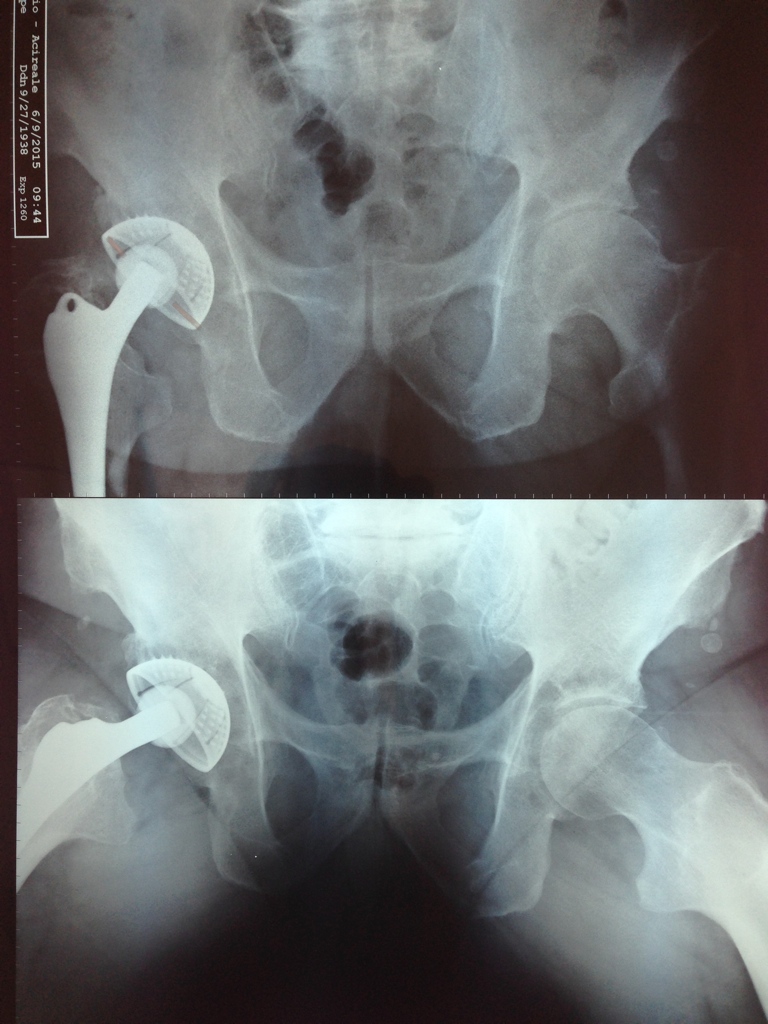

- Una giovane signora con una artrosi dell’anca

- Una frattura di bacino in un Calatino:

Postoperatorio

- Il piacere di un paziente che torna … per farsi operare l’altra anca dopo aver avuto soddisfazione con la prima: